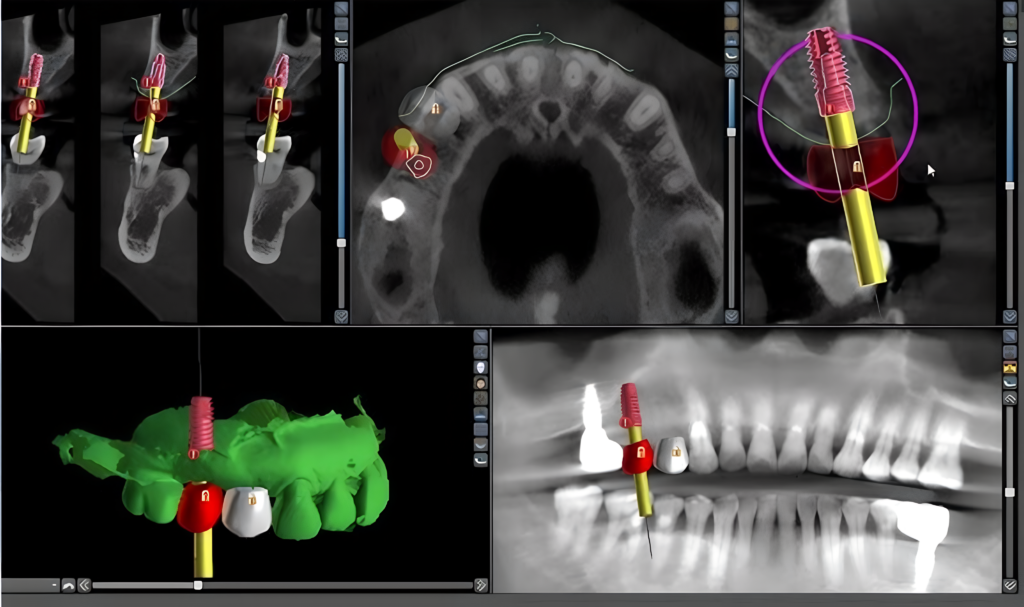

Planejamento Digital 3D

Utilizamos tomografia de alta definição e planejamento digital para ter mais precisão e previsibilidade do tratamento. Sem surpresas, sem achismos.

Cada caso é avaliado de forma criteriosa, com planejamento individualizado e uso de tomografia, garantindo um tratamento preciso e adequado para cada paciente.

- Planejamento com tomografia para máxima precisão